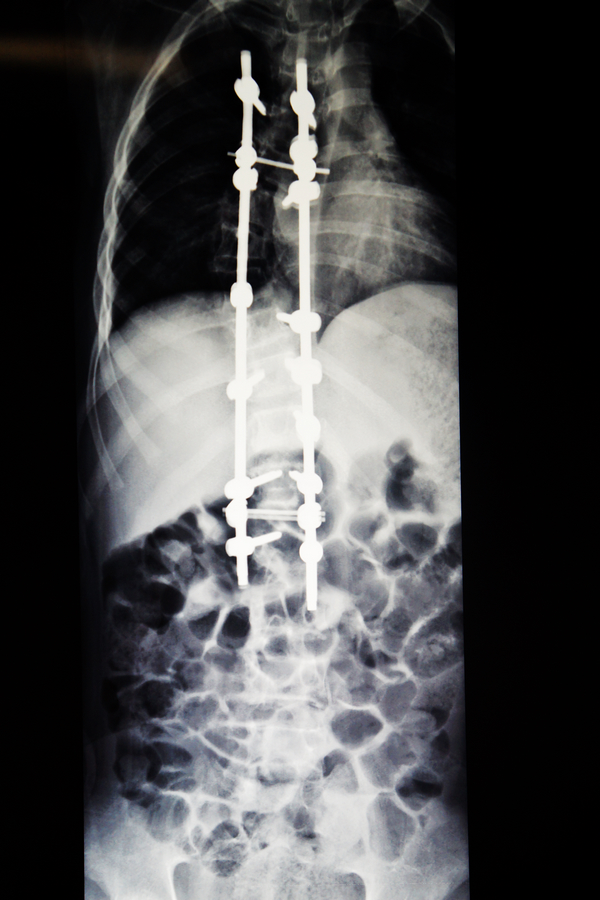

小松的爸妈懵了,他们央求医生一定要想办法帮小松把歪了的背给“扳直”。骨脊柱二区刘汝专主任和鲁世金主任等专家迅速组织了术前科室讨论,一致认为:小松的脊柱侧弯明显,脊柱侧凸严重影响了他的生长发育、外观,同时若放任侧凸发展下去,必然会压迫心脏、肺脏等器官,影响心肺功能,脊柱不平衡还会导致肌肉神经受牵拉,保守治疗无效,同时手术指征明确,宜马上施行手术。结合小松的临床症状和辅助检查,此次手术的目的在于纠正他的脊柱侧弯,恢复脊柱的稳定性,手术方式选择后路脊柱侧凸畸形矫形、椎弓根螺钉内固定植骨、肋骨截骨术。刘汝专主任等专家拟好了周详手术方案,还特别列出了术前术中的注意事项:术前注意测量设计好内固定物放置方式,并预计矫正角度;术中注意熟悉解剖,适当矫形,避免过度纠正,导致脊髓神经牵拉性损伤,固定要牢固;术后给予脱水、营养神经、预防感染等药物治疗。

现在,经过手术后的小松脊柱外观基本恢复了正常,他感到背部没有明显的疼痛,且背部的手术伤口也愈合良好,没有发热头晕头痛和恶心呕吐等不适症状,饮食睡眠都很好,四肢感觉、运动、肌力正常。

小松术后的X光片1